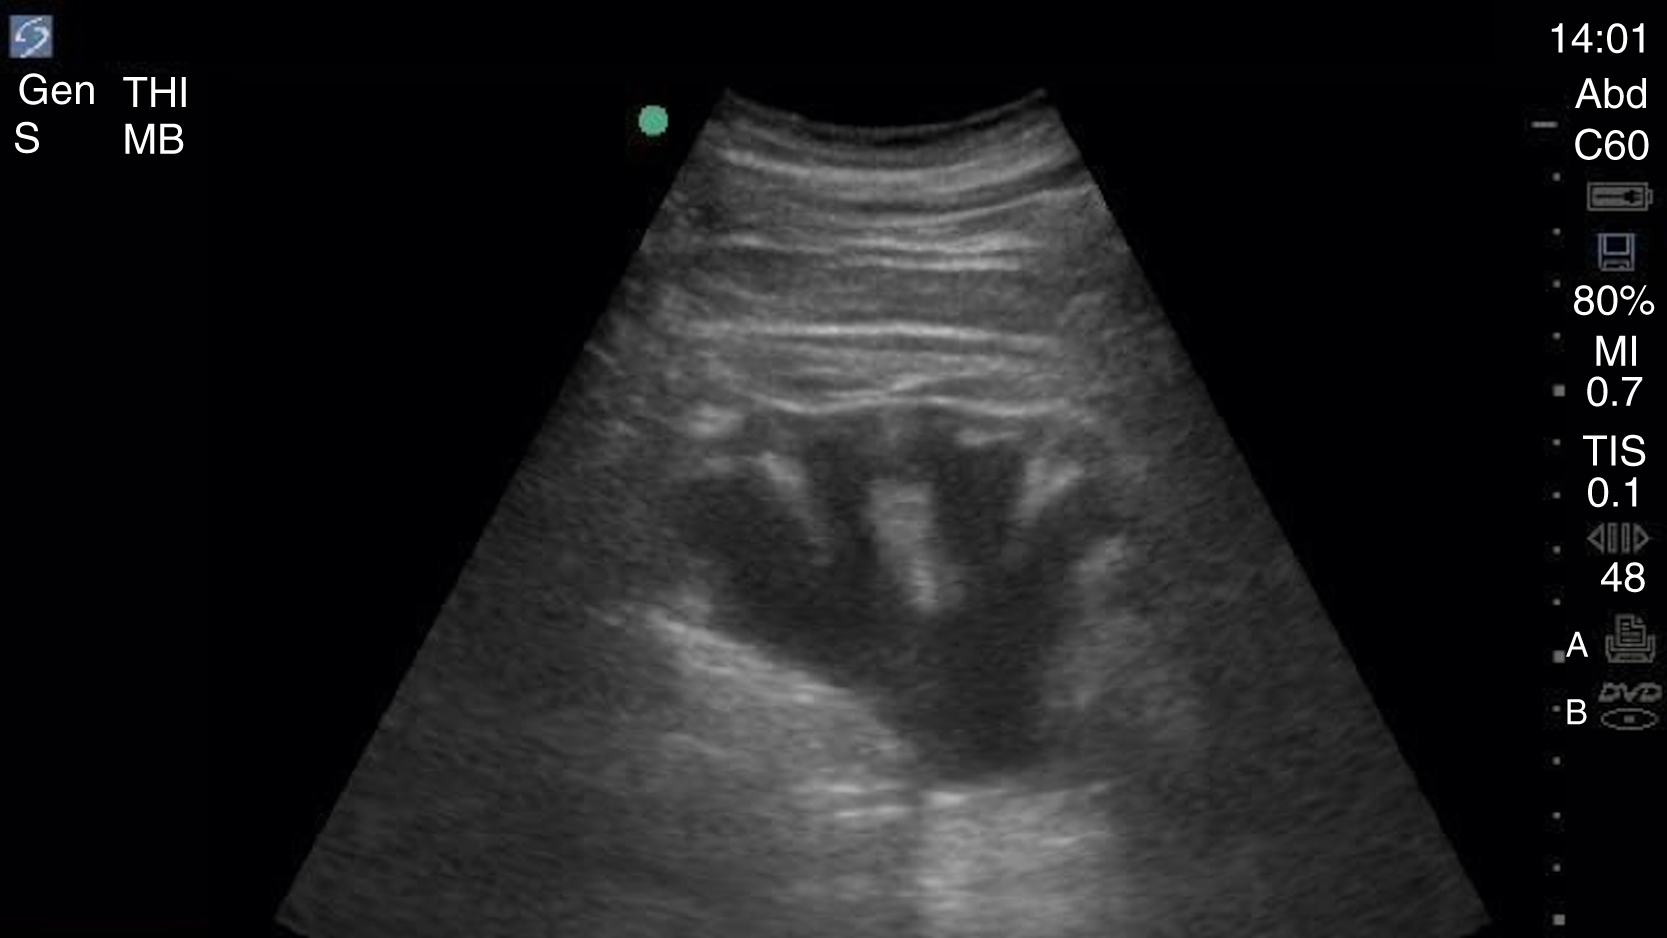

Once the pleural line has been evaluated for sliding, then the determination of intraparenchymal fluid should be made. A lines indicate a dry lung, whereas B lines indicate the presence of fluid within the lung. B lines are vertical hyperechoic reverberation artifacts that arise from the pleura, move with respiration, extend off the screen without fading, and erase the normal A line pattern ( Fig. e3.16 ). Normally found in small numbers in the dependent areas of the lung (atelectasis), the widespread distribution of B lines, typically 3 or more in one lung window, indicates increased interstitial and/or alveolar thickening due to fluid accumulation (edema) or scarring (fibrosis). , As the lung accumulates fluid with consolidation, such as a lobar pneumonia, it can appear echogenic, so-called liver-like (hepatization). When diagnosing pneumonia with lung US, the consolidation needs to be in contact with the pleura to be visible within an intercostal window. Other signs can be seen with pneumonia, but dynamic air bronchograms, hyperechoic areas within bronchi that move with respiration, usually within the consolidated lung, are highly specific for alveolar consolidation. As seen in the E-FAST examination, pleural fluid appears as an anechoic collection above the diaphragm, although internal echoes may be present in cases of chronic, infected, or loculated effusions.